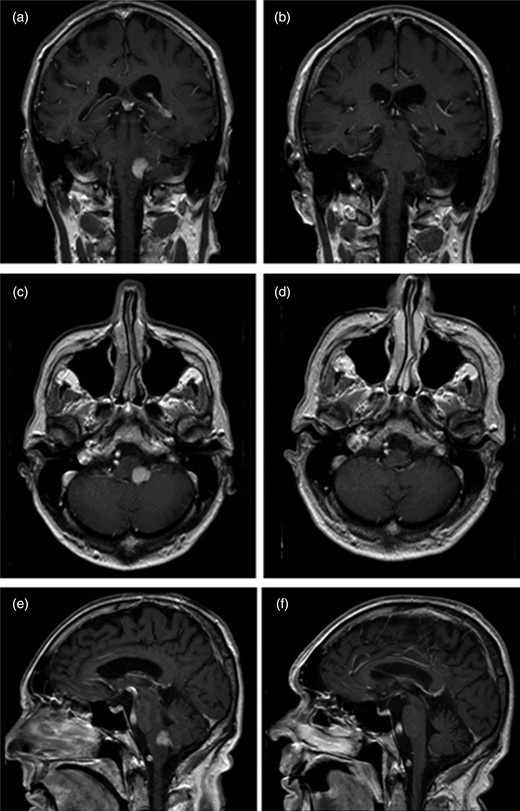

The patient embarked on IDARAM (idarubicin, cytarabine, methotrexate, dexamethasone) chemotherapy followed by two rounds of high-dose methotrexate mono-therapy. Imaging following treatment showed radiological remission and this is also seen on recent scans, now 2 years later (see Fig. 2). While the symptoms of cerebellar dysfunction have largely abated since discharge, the patient has, however, been continually troubled by his cough.

Compares initial T1-weighted gadolinium-enhanced MRI images (seen in panes on left hand side: a, c and e) with those taken following completion of treatment (panes on right: b, d and f). Radiological remission is shown in the post-treatment images.